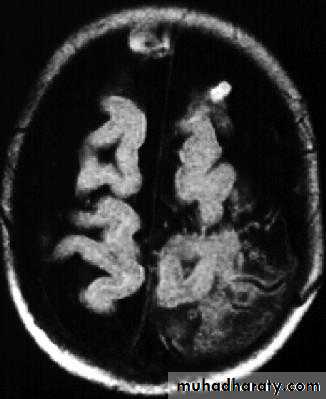

Bacterial Meningitis with cerebral oedema